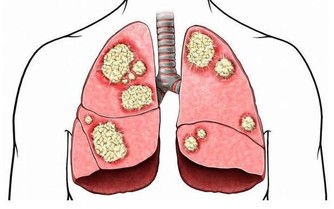

近年來,腸癌的發病率逐年上升,在我國惡性腫瘤發病排第四位。數據顯示,我國每5分鐘就有1人死於大腸癌,絕大多數發現就是中晚期。

更可怕的是,中國腸癌年輕化趨勢特別明顯。美國人腸癌平均發病年齡是69.8歲,但是中國人居然是48.3歲,年輕了20歲,很多都是30~40歲的中年人。

大腸癌早期無症狀,或症狀不明顯,僅感不適、消化不良、大便潛血等。隨著癌腫發展,症狀逐漸出現,表現為大便習慣改變、腹痛、便血、腹部包塊、腸梗阻等,伴或不伴貧血、發熱和消瘦等全身症狀。腫瘤因轉移、浸潤可引起受累器官的改變。大腸癌因其發部位不同而表現出不同的臨床症狀及體徵。